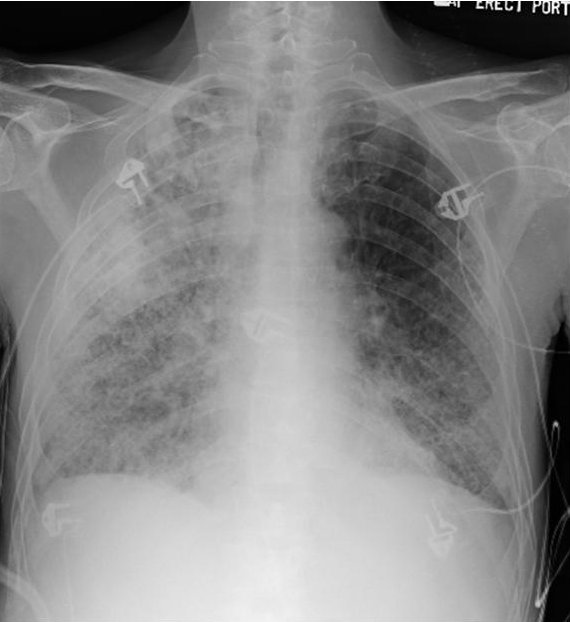

He was initially admitted to the general medical floor for treatment of community-acquired pneumonia (see Figure 1) and for the prevention of delirium tremens. He was initiated on ceftriaxone, azithromycin, thiamine and folic acid. Diazepam was initiated and titrated using the Clinical Institute Withdrawal Assessment for Alcohol Scale (CIWAS-Ar), a measure of withdrawal severity (1). By hospital day 5, his respiratory status continued to worsen, requiring transfer to the intensive care unit (ICU) for hypoxemic respiratory failure. His neurologic status had also significantly deteriorated with worsening confusion, memory loss, drowsiness, visual hallucinations (patient started seeing worms) and worsening upper extremity tremors without generalized tremulousness despite receiving increased doses of benzodiazepines.